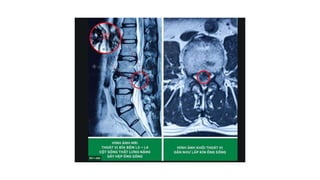

 Chụp cộng hưởng từ (MRI): hình hình ảnh trực tiếp của TVĐĐ

4. Chẩn đoánthoát vị đĩa đệm 4.1. Chẩn đoán xác định 4.1.2.Chẩn đoán cận lâm sàng  Chụp cộng hưởng từ (MRI): hình hình ảnh trực tiếp của TVĐĐ  Phương pháp chụp cắt lớp vi tính đĩa đệm: độ nhậy và độ đặc hiệu không cao trong chẩn đoán TVĐĐ.  Phương pháp chụp đĩa đệm (discography): hình ảnh trực tiếp về nhân nhầy của đĩa đệm.  Phương pháp chụp khoang ngoài màng cứng phía trước: hình ảnh gián tiếp đĩa đệm TV  Phương pháp chụp tĩnh mạch gai sống thắt lưng: => gián tiếp thấy hình ảnh đĩa đệm bị thoát vị.